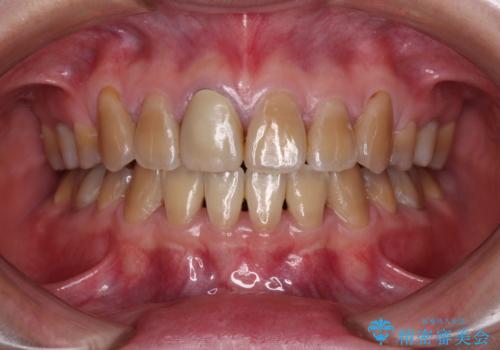

上下の正中がずれていましたが、抜歯矯正であったので、極力正中位置を合わせるように治療を進めて行きました。

顎間ゴムの使用などにより、正中位置を改善することができました。